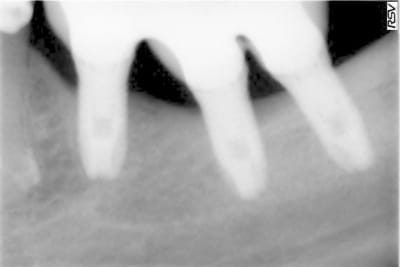

ouvre les yeux: la crétérisation est importante à 4 mois ou à un an

il y a cratérisation dans prseque tous les cas de figure: juxta ou infra-crestal.

la cratérisation apparait avec la mise en place des vis de cicatrisation